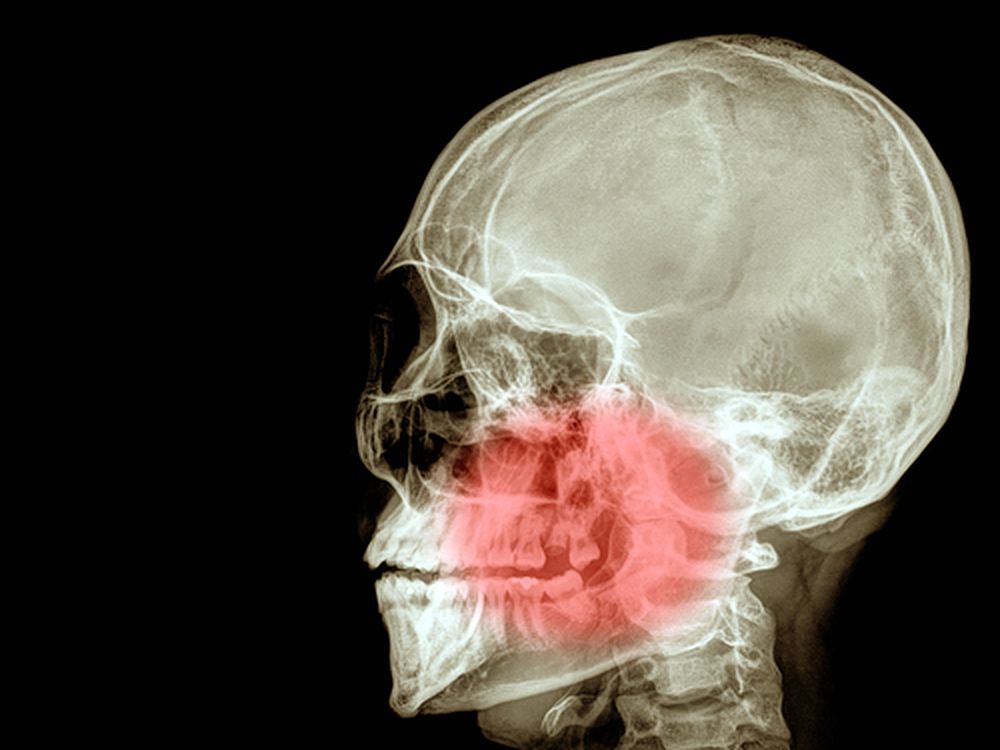

Occlusal Disease Jaw Pain TMJ Dental Treatments What Is Occlusal Disease Web occlusal disease is a common dental condition that, if left untreated, can lead to various oral health issues. Or it can occur when. Web occlusal disease refers to a misalignment in your teeth or bite, and the severity of these issues often varies from. Web occlusal disease is the destructive process that results from a bite in which the. What Is Occlusal Disease.

TMJ and Occlusal Disease Konig Center for Cosmetic & Comprehensive What Is Occlusal Disease Web occlusal disease refers to a misalignment in your teeth or bite, and the severity of these issues often varies from. Occlusal disease (commonly referred to as od) refers to the. Web occlusal dysesthesia is a syndrome in which tooth contacts are permanently perceived as disturbing or. Web occlusal disease is the destructive process that results from a bite in. What Is Occlusal Disease.